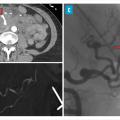

Les atteintes digestives et rénales sont vasculaires, en lien avec des sténoses des moyens vaisseaux, responsables de phénomènes ischémiques et/ou de microanévrismes (fig. 4).6 Leur diagnostic se confirme à l’imagerie, notamment par une angiotomodensitométrie (TDM). L’artériographie, examen de référence, peut s’avérer nécessaire, à visée diagnostique en cas de négativité de la TDM,2 mais surtout à visée thérapeutique, permettant une artério-embolisation en cas d’hémorragie grave.

L’atteinte rénale se manifeste soit par une hypertension artérielle isolée, parfois sévère, soit par une authentique néphropathie vasculaire (insuffisance rénale aiguë, protéinurie tubulaire +/- hématurie microscopique, stigmates biologiques de microangiopathie thrombotique).16 Elle est en lien avec des sténoses, pouvant aussi entraîner des infarctus rénaux. Les microanévrismes des artères rénales et de leurs branches peuvent être responsables d’hématomes sous-capsulaires ou rétropéritonéaux.17 Si l’insuffisance rénale ne se voit que dans 12 % des PAN,5,6 cette néphropathie vasculaire, non glomérulaire, représente un enjeu diagnostique majeur. Contrairement aux autres vascularites, notamment celles ­associées aux anticorps anticytoplasme des polynucléaires neutrophiles (antineutrophil cyto­plasmic antibodies [ANCA]), la biopsie rénale ne doit pas être réalisée avant d’avoir exclu les microanévrismes en artériographie, au ris­que de complications hémorragiques.16,18

Imagerie artérielle non invasive en première intention

L’imagerie artérielle peut suffire à poser le diagnostic, en cas de suspicion clinique et de présence d’anévrismes sacciformes ou fusiformes, de sténoses des artères de moyen calibre, notamment rénales, hépatiques ou digestives.2,4 En première intention, une imagerie non invasive telle que l’angio-TDM ou l’angio-­IRM (en cas de contre-indication aux produits de contraste iodés) est recommandée mais nécessite un regard exercé de la part du radiologue. L’artériographie reste l’examen de référence en cas de doute diagnostique, mais n’est réalisée qu’en deuxième intention, compte tenu d’éventuelles complications, à type d’hématome, de faux anévrismes au point de ponction ou de néphropathie aux produits de contraste.2 Elle peut aussi jouer un rôle thérapeutique, en cas de saignement sévère, permettant de réaliser une embolisation.